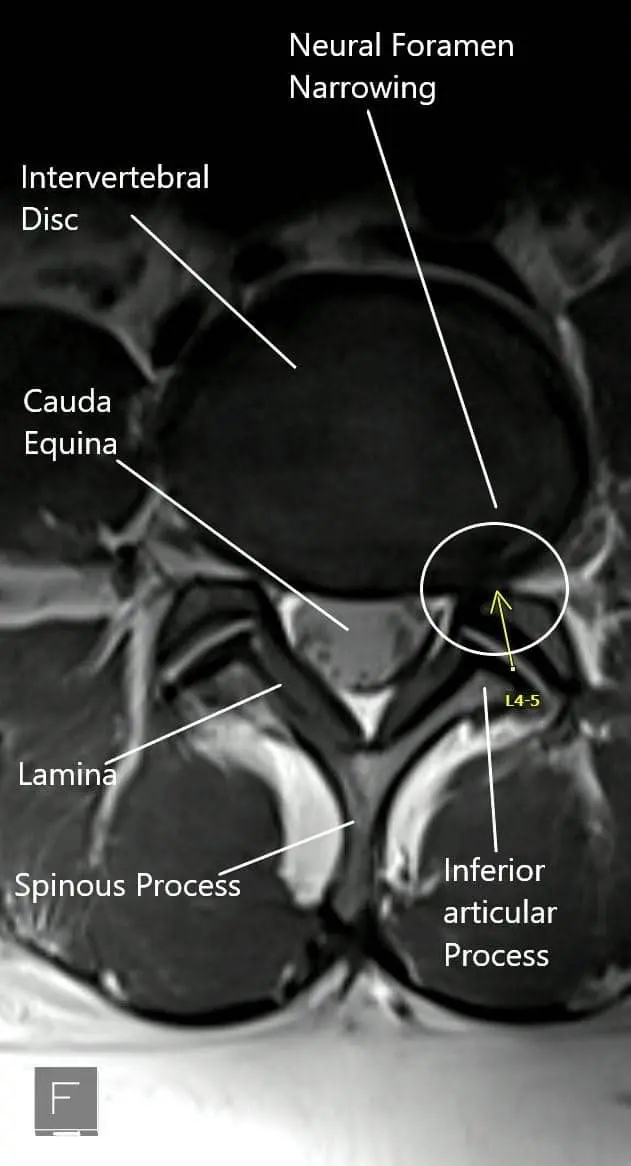

MRI showing the axial section of the lumbar spine with neural foramen narrowing.

The Sciatic nerve is formed by the collection of nerve roots L4, L5, S1, S2, and S3. The nerve roots arise from the distal part of the spinal cord. The roots exit the vertebral column through neural foramen.

The dural sac containing all the nerve roots from cauda equina lie inside the central canal. The central canal is bound by the vertebral body and the intervening intervertebral disc in the front and the lamina in the back. The facet joints are present near the neural foramen on the sides of the vertebral canal.